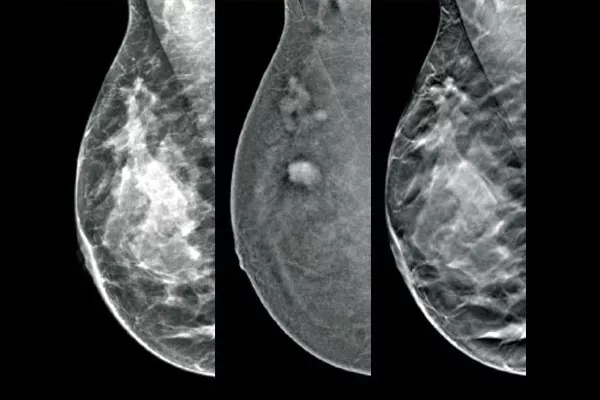

The Affirm™ Contrast Biopsy Solution enables the targeting and acquisition of breast tissue in lesions identified during contrast-enhanced mammography (CEM). Designed to maximise workflow efficiency while improving the patient experience, the complete Contrast Biopsy solution simplifies the breast biopsy process,* even for challenging procedures.

Target and biopsy lesions identified with 2D contrast-enhanced mammography through a stereotactic-based procedure, with a comparable diagnostic performance to a breast MRI procedure.1,2 Compare post-marker images in the same modality as the initial diagnostic contrast exam.

Affirm Contrast Biopsy software allows you to biopsy lesions identified during the I-View™ contrast-enhanced 2D mammogram. By leveraging the ability to provide 2D, contrast-enhanced, and tomosynthesis images under one compression,4 The Affirm Upright Breast Biopsy Guidance System enables a quick transition from screening to biopsy, leveraging the same proven imaging chain5 as the mammography system to improve 3D™ visualisation of suspicious lesions.**

An Efficient & Cost-Effective Alternative to MRI

Functional imaging, using CEM, compares favourably to breast MRI with similar sensitivity, higher specificity, and higher positive predictive value.7,8 In addition, CEM provides a cost-effective diagnostic imaging alternative9 compared to MRI, with a shorter procedural time.7,10